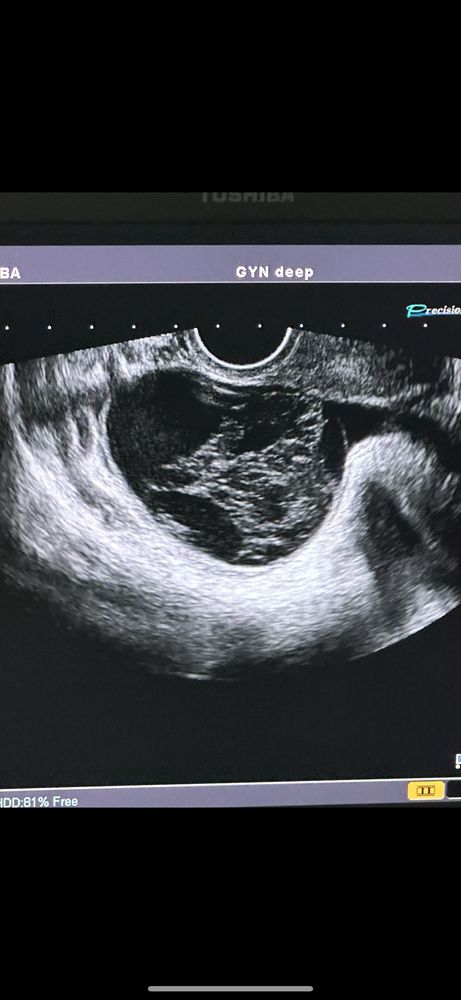

Киста 7см и тошнота второй цикл

Изначально начало тошнить в прошлом цикле, как раз когда и нашли кисту, была задержка 2 недели, тошнота так и соблюдалась, месячные вызывали Дюфастоном, тошнота усилилась, с месячными киста не ушла, а только выросла с 6,2 до 6,8